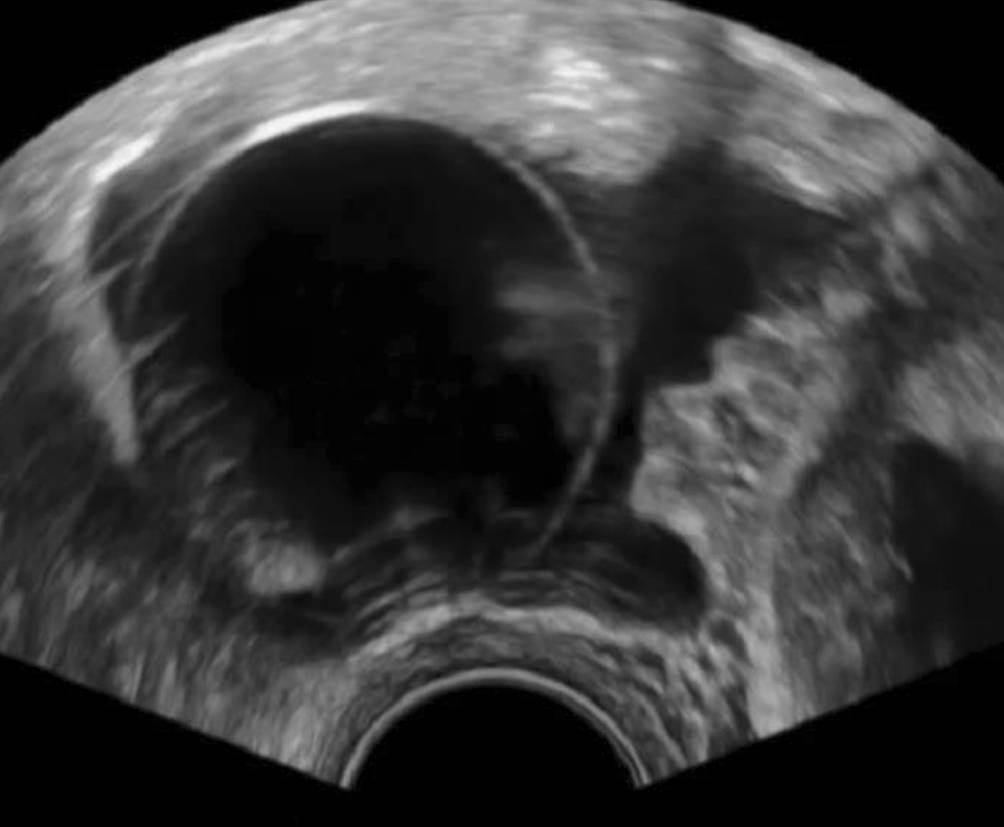

Reservoire von Kathetern und künstlichen Sphinkteren

Spätestens beim Einbringen der Vaginalsonde in die Scheide sollte bei der Untersuchung ein liegender Blasenkatheter aufgefallen sein, und das von ihm hervorgerufene Bild einer kreisrunden Struktur in dem Bereich vor dem Uterus sollte nicht allzu viel Staunen auslösen (Abb. 1). Wenn etwas Harn in der Blase ist, ist das Bild sofort plausibel (Abb. 2), wenn nur der Katheter in der Blase liegt, kann dies zunächst verwirren, wenn man nicht daran denkt.

Abb. 1

Kreisrunde, homogen echodens demarkierte, echoarme Struktur mit zentralem echodensem Streifen anterior des Uterus gelegen … was ist das?

Abb. 2

Sobald die Blase nur etwas gefüllt ist, löst sich das Rätsel von Abb. 1 und es zeigt sich der Ballon eines liegenden Blasenverweilkatheters